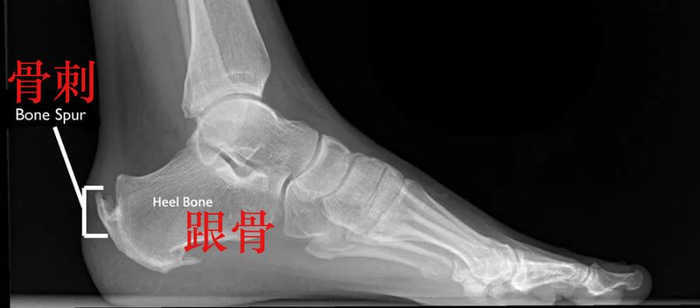

另外,在年纪较大的运动者中,经常出现的是 止点跟腱炎。患有这种跟腱炎的运动者通常会在跟骨位置出现疼痛,并在运动后会有疼痛加重的情况。随之而来的是,跟腱附着点炎症病变,肌腱会出现钙化转变为骨质,也就是我们常说的“骨刺”。

骨刺(photo via Bouldercentre for Orthopedics&Spine)